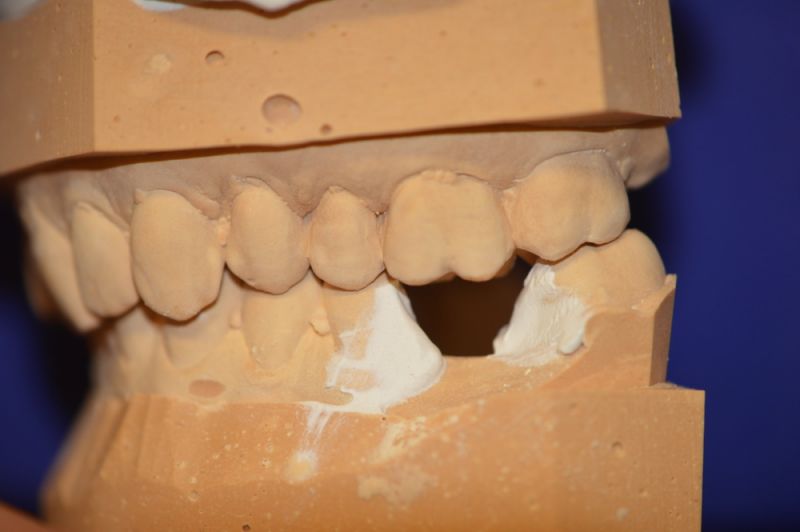

Es läuft dfas Nachweisverfahren einer CMD unter Einsatz eines adjustierten Aufbissbehelfs.

Deutlich erkennbar die Nonokklusion in neuromuskulär zenmtrierter Bisslage